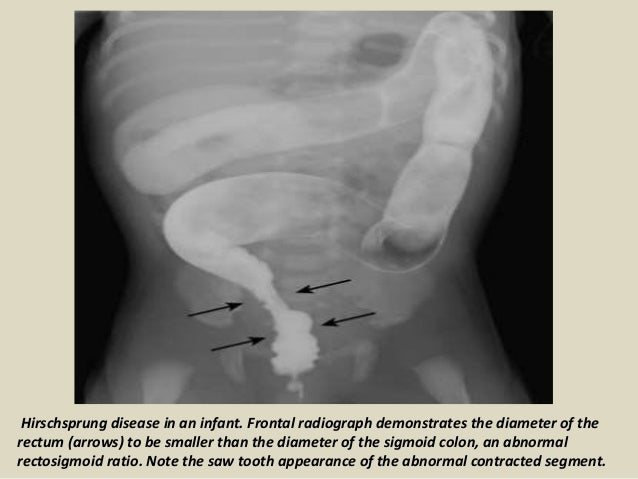

Barium enema demonstrates a reduced caliber rectum and sigmoid the rectum is smaller than the descending.